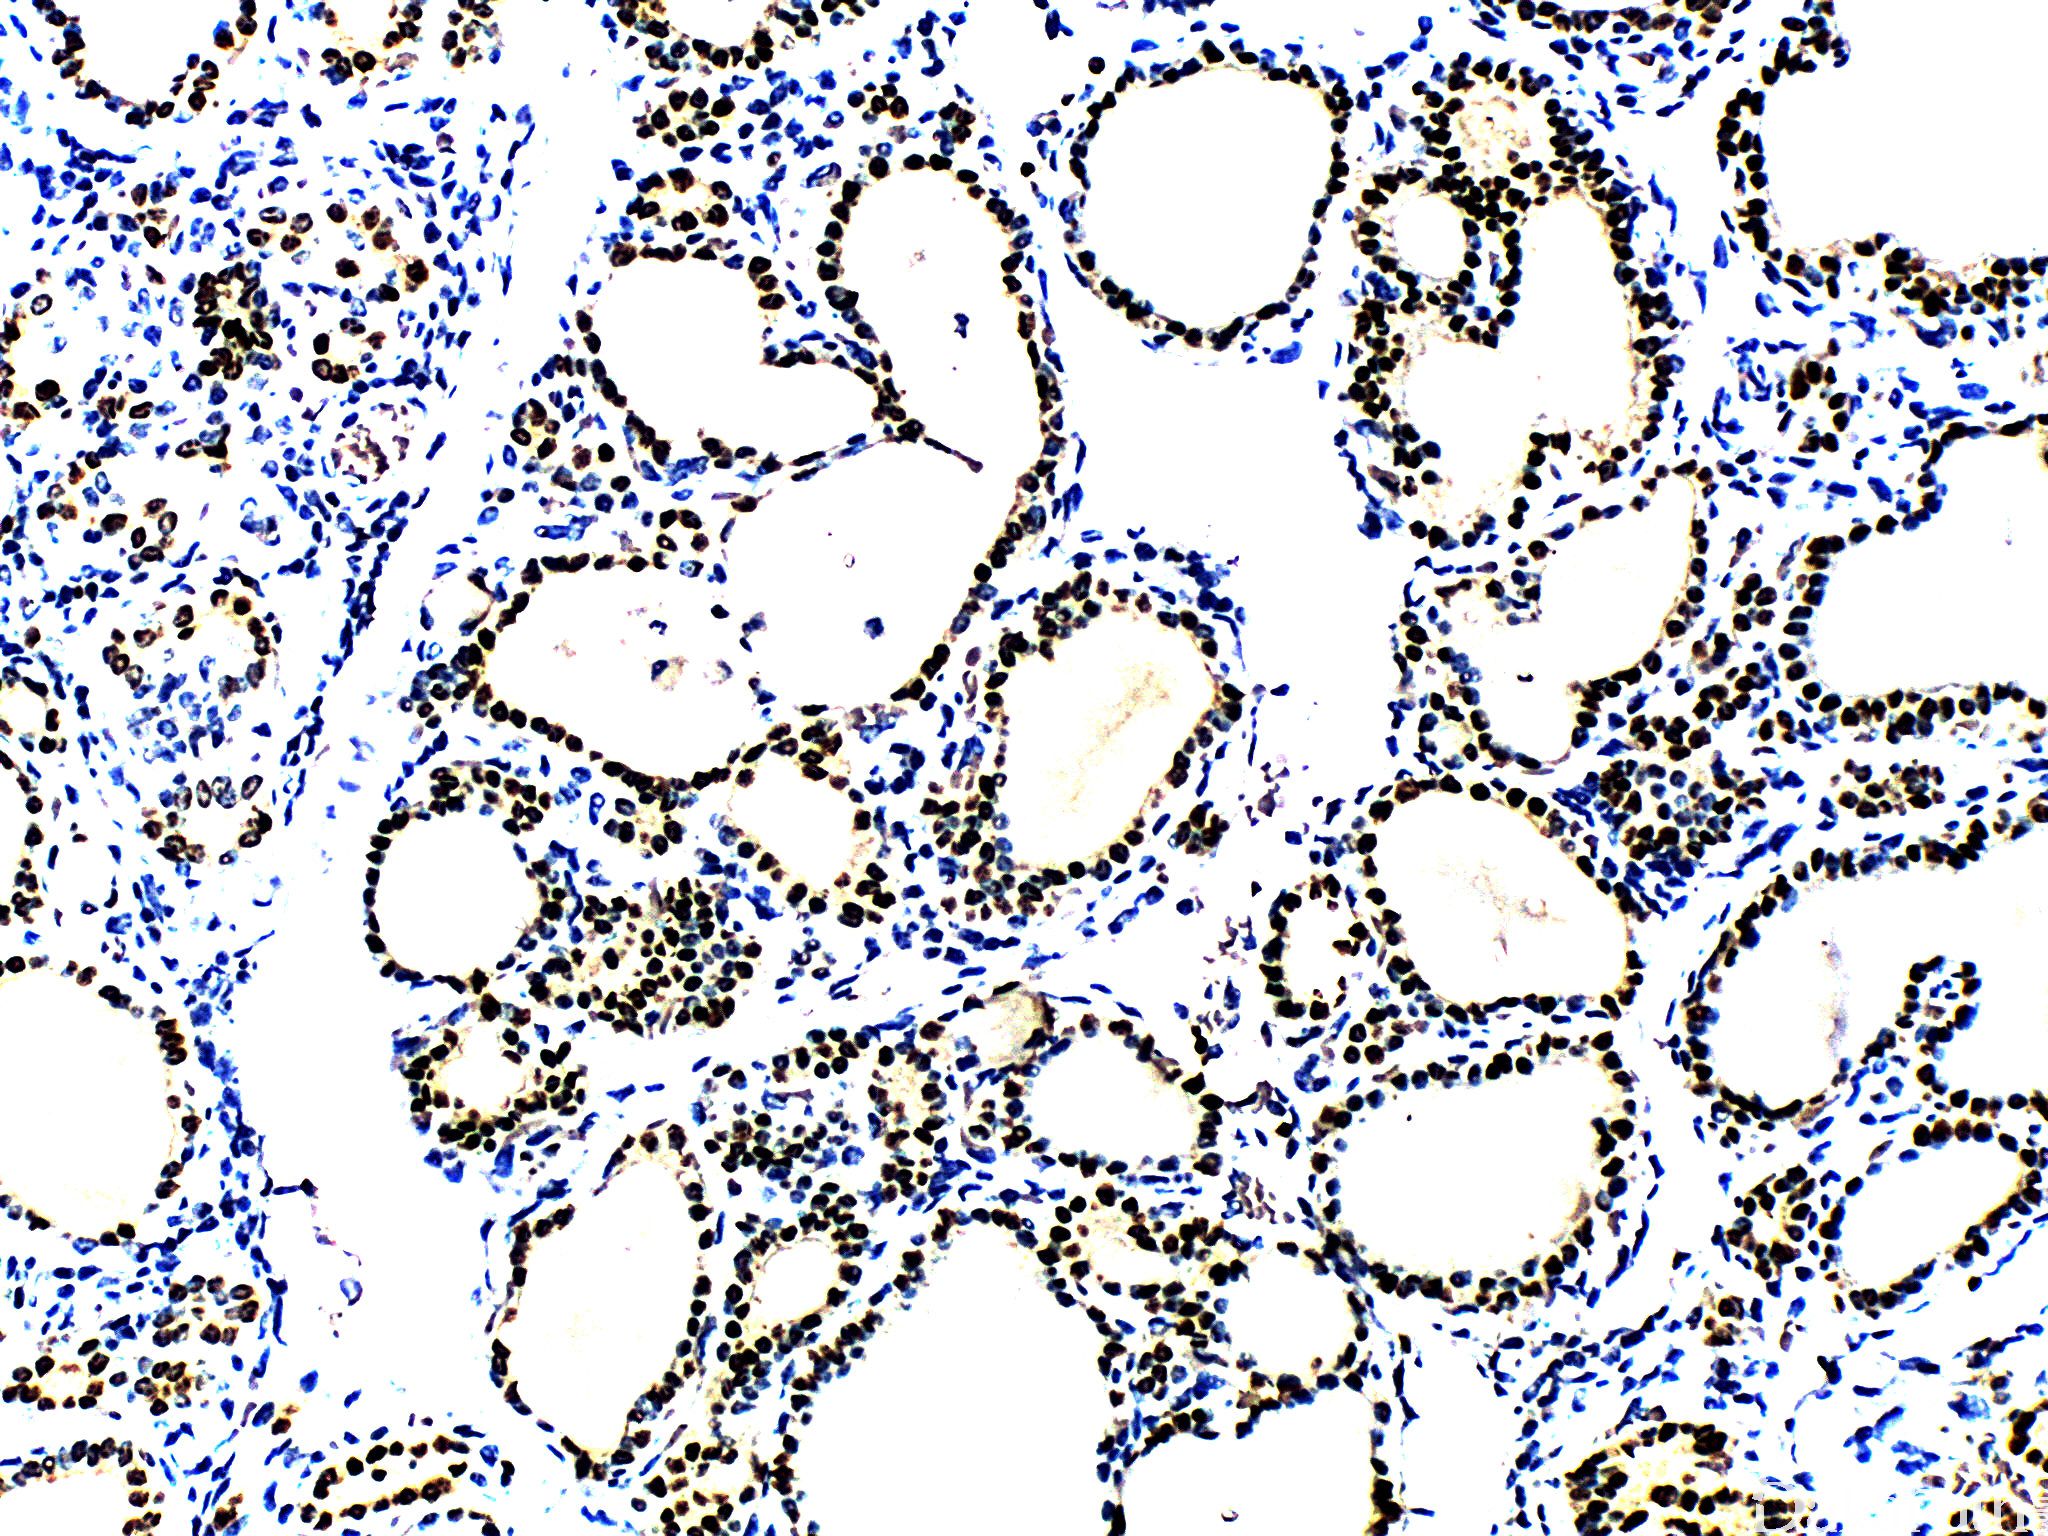

PAX8

核转绿因子,PAX(pair box gene)家族成员之一。表达于甲状腺、肾导管组织、副中肾管组织及相关肿瘤中,对于转移性肾细胞癌,PAX-8 的敏感性优于 CD10 和 RCC。

阳性表达主要见于肾肿瘤(肾细胞癌及肾集合管癌)、苗勒管肿瘤(80-85%)、甲状腺肿瘤;其它阳性表达肿瘤包括胸腺瘤/癌和胰腺神经内分泌肿瘤。

信号定位: 典型的为胞核阳性,胞质或包膜着色为非特异性着色。

几乎全部阳性(≥95%的病例阳性): 宫颈高级别鳞状上皮内病变、胸腺瘤,A 型、透明细胞乳头状肾细胞癌、乳头状肾细胞癌、肾混合性上皮和间质肿瘤,间质成分、肾细胞癌、透明细胞肾细胞癌、管囊性肾细胞癌、肾混合性上皮和间质肿瘤,上皮、甲状腺滤泡性腺瘤、子宫内膜腺癌,NOS、甲状腺滤泡性癌、甲状腺乳头状癌、良性胸腺瘤、甲状腺癌显示胸腺样分化、卵巢低级别浆液性癌、肾母细胞瘤、子宫内膜黏液腺癌、卵巢高级别浆液性癌、淋巴瘤、膀胱透明细胞癌、宫颈透明细胞癌、卵巢恶性 brenner 瘤、阴道透明细胞腺癌,DES 相关、肾横纹肌样肾细胞癌,横纹肌样成分、肾髓质癌、高分化乳头状间皮瘤、甲状旁腺腺瘤、卵巢透明细胞癌、甲状腺腺瘤、卵巢浆液性交界性肿瘤/非典型增生性浆液性肿瘤、肾混合性间质和上皮肿瘤、中肾腺瘤、囊性肾瘤、宫颈原位腺癌、卵巢浆液性癌、肾黏液管状和梭形细胞癌、肾源性腺瘤、卵巢表面上皮包涵腺体和囊肿